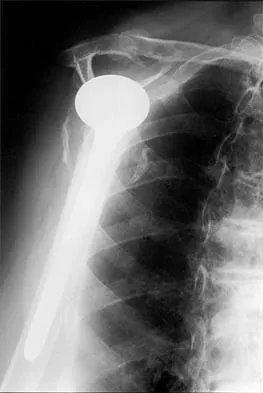

A 62-year-old man with a long history of right shoulder pain and weakness is scheduled to undergo hemiarthroplasty. Based on the radiographs shown in Figures 6a through 6c, what preoperative factor will most affect postoperative functional outcome?

Explanation

The radiographs reveal osteoarthritis and proximal humeral head migration. Integrity of the rotator cuff must be questioned based on these radiographic changes. The status of the rotator cuff is the most influential factor affecting postoperative function in shoulder hemiarthroplasty. The coracoacromial ligament provides a barrier to humeral head proximal migration in the face of a rotator cuff tear. The radiographs do not indicate significant humeral head or glenoid erosion. Acromioclavicular arthritis is often asymptomatic. Iannotti JP, Norris TR: Influence of preoperative factors on outcome of shoulder arthroplasty for glenohumeral osteoarthritis. J Bone Joint Surg Am 2003;85:251-258.